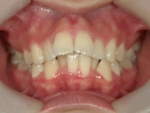

叢生(そうせい)

歯の生えるスペースが足りなかったり歯が大きいために、でこぼこに生えたり、重なって生えている状態です。乱杭歯(らんぐいば)ともいいます。犬歯が飛び出た状態の八重歯(やえば)も叢生の一種です。